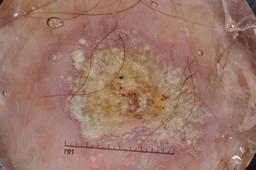

ISIC-DICM-17K (ISIC Dermoscopic Images and Clinical Metadata 17K) is a curated and balanced dataset derived from the International Skin Imaging Collaboration (ISIC) Archive Gallery. It comprises 17,060 dermoscopic images and clinical metadata (8,530 melanoma and 8,530 non-melanoma classes).

For more details, please follow the project’s GitHub repository: https://github.com/mmu-dermatology-research/isic-dicm-17k

This dataset was used in this study and benchmark to explore the effectiveness of multimodal learning for skin lesion classification:

S. Ahammed, X. Cui, W. Lu and M. H. Yap, "Skin Lesion Classification using Dermoscopic Images and Clinical Metadata: Insights from Multimodal Models," 2025 IEEE/CVF Conference on Computer Vision and Pattern Recognition Workshops (CVPRW), Nashville, TN, USA, 2025, pp. 222-230, DOI: 10.1109/CVPRW67362.2025.00027